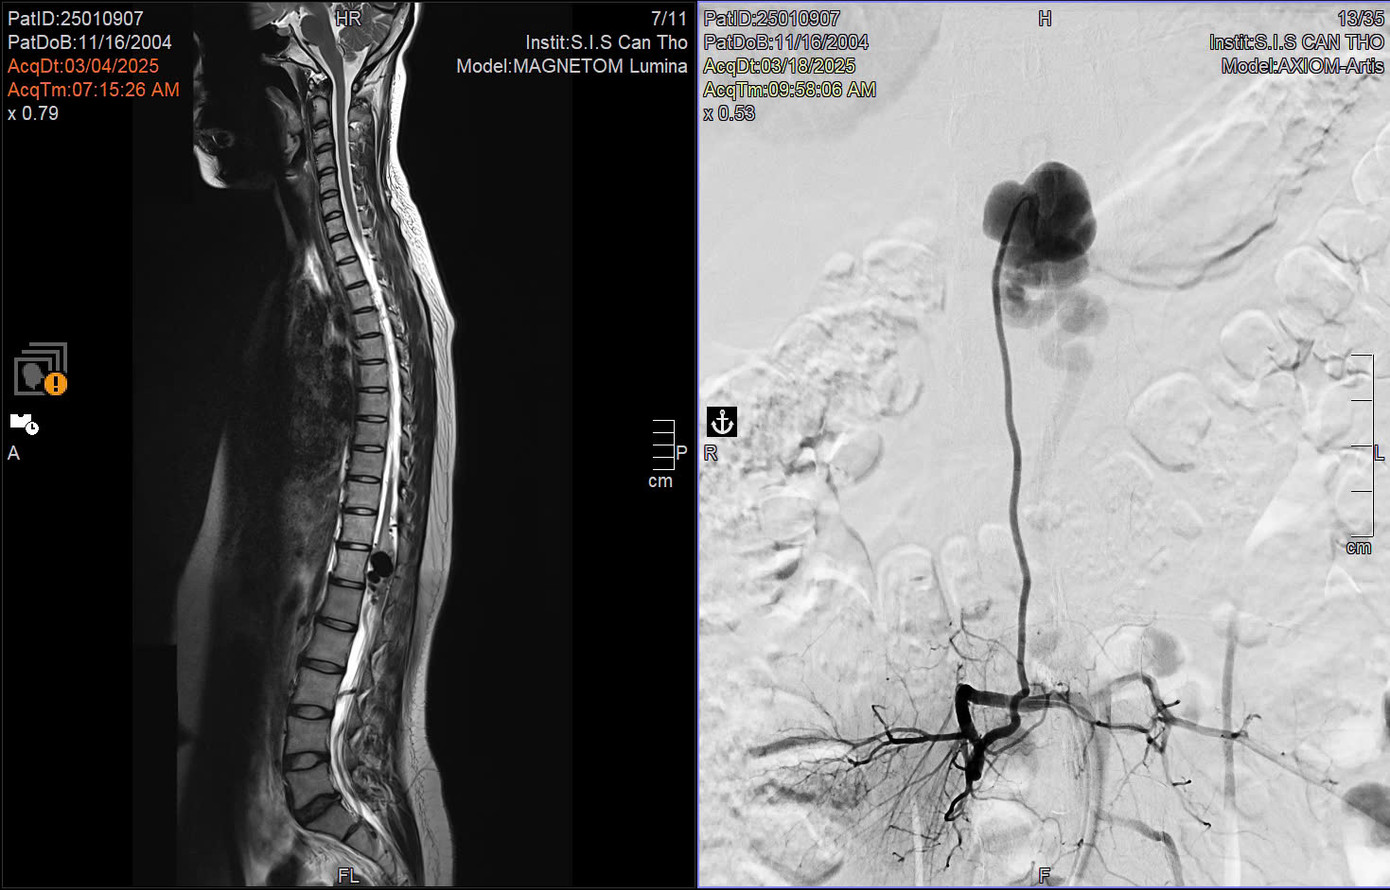

| Hình ảnh kiểm tra phát hiện vị trí dị dạng mạch máu tủy ở bệnh nhân |

N. được người quen giới thiệu đến bệnh viện S.I.S Cần Thơ và được chỉ định chụp cộng hưởng từ (MRI). Từ kết quả hình ảnh học, các bác sĩ phát hiện khối dị dạng mạch máu lớn chèn ép vùng tủy sống, gây phù tủy và tổn thương hệ thần kinh nghiêm trọng.

TS.BS Trần Chí Cường, Giám đốc Bệnh viện Đa khoa S.I.S Cần Thơ cho biết: "Thông thường, đường kính tủy sống khoảng 2cm. Tuy nhiên, ở bệnh nhân này, túi phình dị dạng lên tới gần 2,4 cm, chèn ép hoàn toàn vùng chóp cùng tủy – nơi có chùm đuôi ngựa chi phối vận động hai chân. Đây là nguyên nhân khiến bệnh nhân đau dai dẳng và yếu cơ tiến triển”.

“Chúng tôi đã phải can thiệp nhiều bước, đầu tiên là gây tắc dòng máu bất thường giữa động và tĩnh mạch tủy, sau đó phẫu thuật lấy bỏ túi phình dị dạng. Rất may mắn là can thiệp kịp thời, khi tổn thương tủy còn có thể hồi phục” -BS.Cường nói.